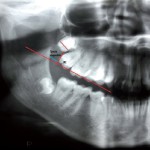

Dislocazione del terzo molare durante chirurgia: complicanze e soluzioni

La chirurgia del terzo molare incluso, superiore e soprattutto inferiore, rappresenta una fra le competenze maggiori del chirurgo orale. Il livello di complessità dell'intervento è ampiamente variabile in ragione della posizione del dente e del suo stato. Una complicanza non propriamente comune è la dislocazione dell'elemento – o di un suo frammento – negli spazi anatomici circostanti a seguito delle manovre estrattive.